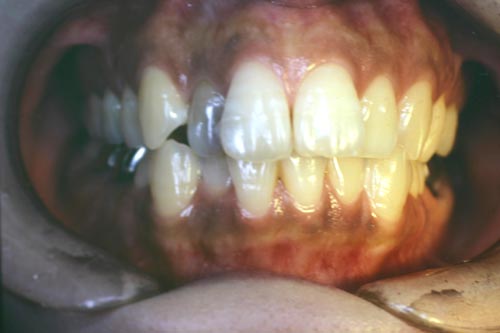

50代で歯周病のもある患者様の矯正症例

Before

特に奥歯が抜いてあるため、奥歯の本数がこれ以上少なく出来ない方です。これだけの強い不正咬合を非抜歯で治した症例です。年齢的にも難しい症例でしたが、かなりきれいに治り、 患者様自信が大変満足された症例です。

年齢 50代

治療期間 1年6ヶ月

治療費用 1,000,000円

治療のリスク 歯周病が進行するリスクがある